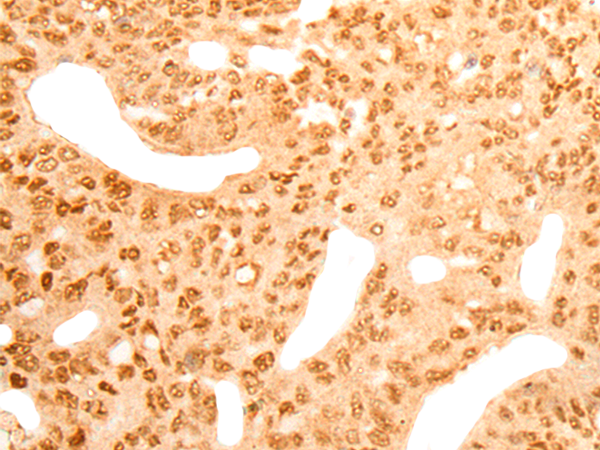

Applications: |

ELISA, IHC |

IHC positive control: |

Human colorectal cancer and Human gastric cancer |

IHC Recommend dilution: |

25-100 |